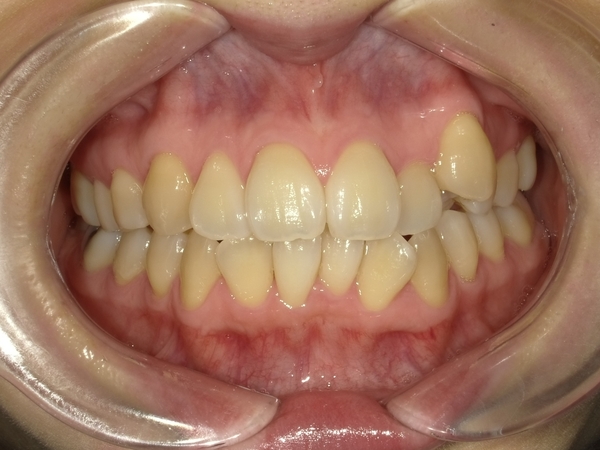

ガタガタとした歯並びや八重歯(叢生)CASE68